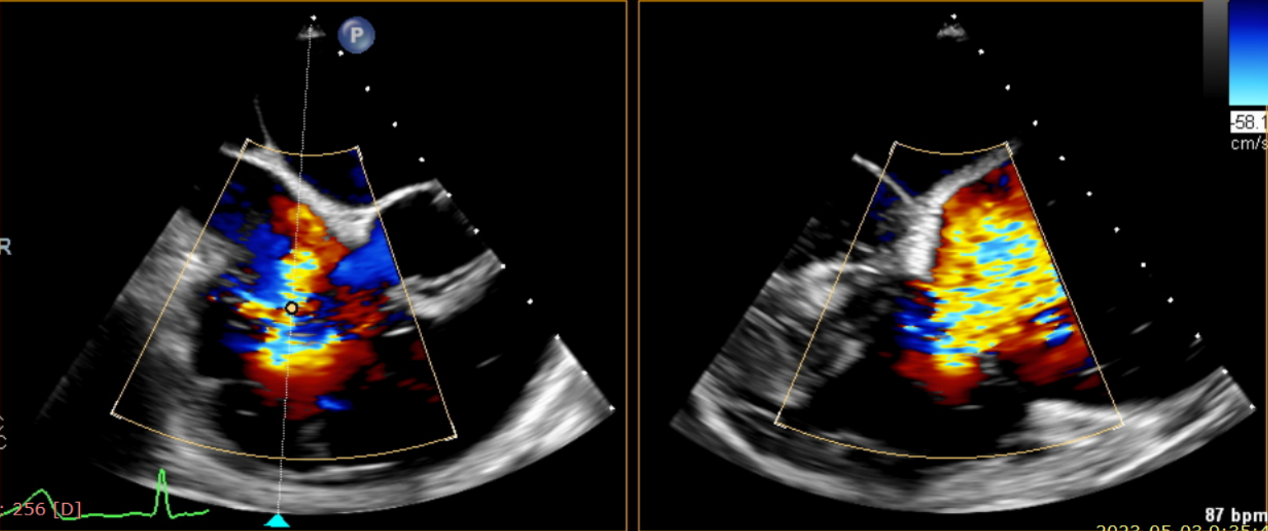

術(shù)中輸送器在超聲引導(dǎo)下調(diào)整位置